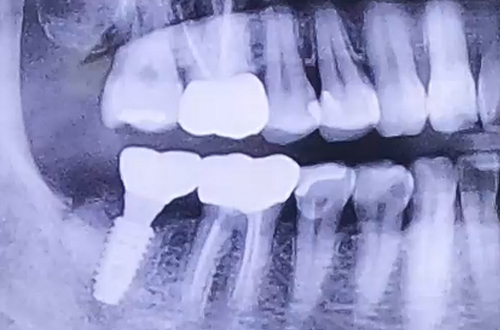

AFTER

치료 유형 발치 후 임플란트

치아에 엄청난 통증을 호소하며 급하게 내원해주신 환자분이십니다.

살펴보니 이미 오래 전에 치료가 다 되었다고 생각했던 충치 치료를 했던 치아가 크게 쪼개진 상태였는데요.